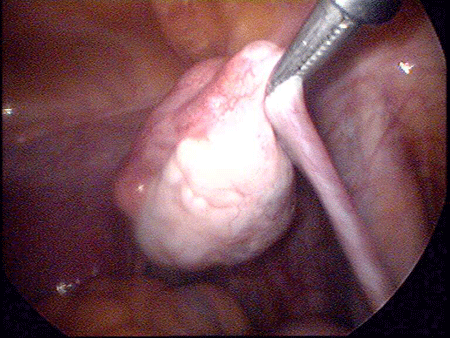

先天性无阴道手术

对于先天性无阴道的“石女”可用压迫扩张法和阴道成形术矫治。所谓压迫扩张法,就是在相当于阴道外口的浅窝处,用光滑的钝头木制圆棒施加机械性压力,每日压迫2次,每次20分钟,约经3个月左右,浅窝可达7-8厘米深度。如此压迫扩张出来的阴道,基本可满足性生活的需要。